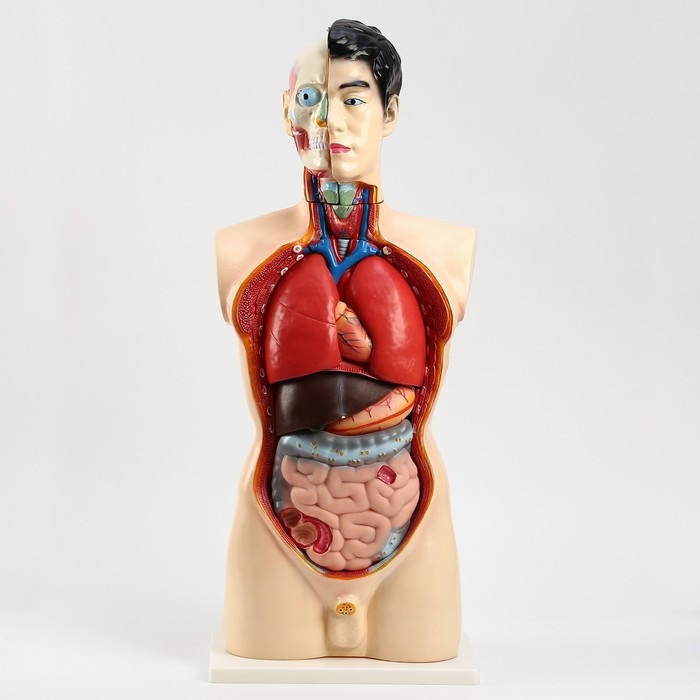

ЕКБ 41

No Brand, артикул: 7072360